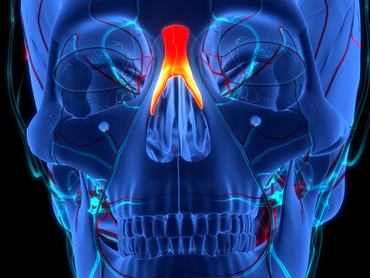

5. kérdés

Melyik csont látható kiemelve a képen?

ékcsont

orrcsont

szemcsont